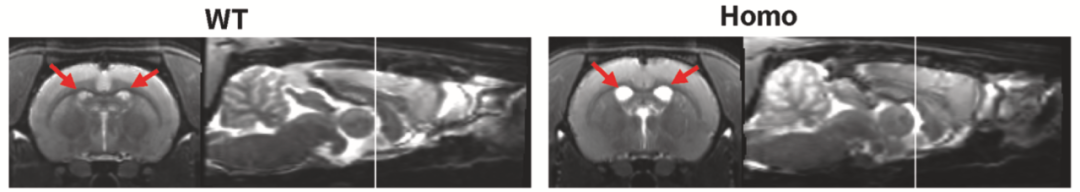

此外,這個大鼠模型還表現(xiàn)出由細胞凋亡和壞死性凋亡介導(dǎo)的神經(jīng)元死亡,以及大腦皮層的嚴(yán)重萎縮,從MRI圖像上可以觀察到腦室擴大。而無論是轉(zhuǎn)基因的“一代小鼠模型”[5],還是基因敲入的“二代小鼠模型”[6],都沒有出現(xiàn)神經(jīng)元的死亡或腦萎縮。

冠狀面上,與 WT 相比,純合AppNL-G-F大鼠的側(cè)腦室擴大